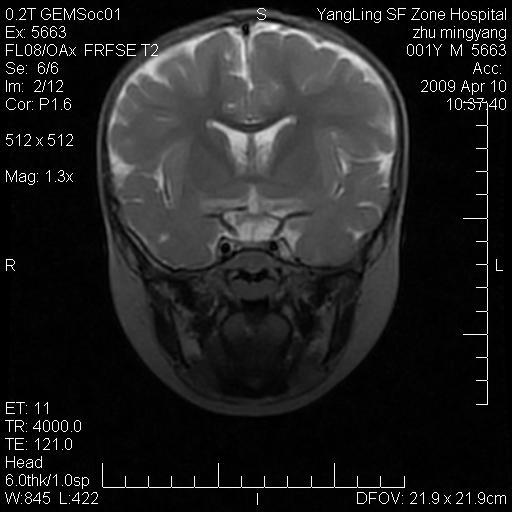

患者:1岁半,两天前外伤收住我院,ct检查小脑占位

考虑星形细胞瘤,建议增强

髓母细胞瘤或血管母细胞瘤,增强后可以鉴别;影像资料见 <。鱼博浪老师的《中枢神经系统ct与mr鉴别诊断》 小脑部肿瘤章节。

髓母细胞瘤或血管母细胞瘤!支持!

支持考虑髓母细胞瘤

考虑----髓母细胞瘤可能性大

考虑髓母细胞瘤或室管膜瘤。

支持髓母细胞瘤。

考虑髓母细胞瘤。

考虑髓母细胞瘤或星形细胞瘤

考虑髓母细胞瘤.

考虑髓母细胞瘤可能性大。

小脑肿瘤.考虑髓母细胞瘤可能.

就病灶部位及临床资料首先考虑髓母.